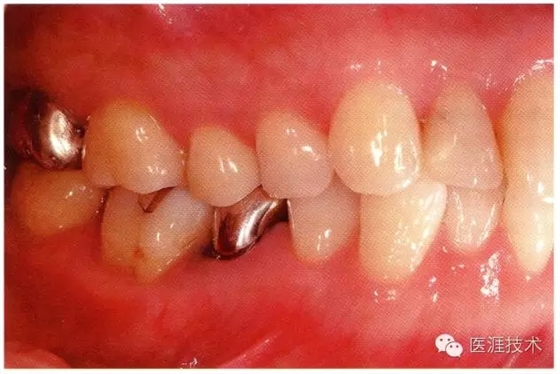

28歲女性的健康口腔內(nèi)部

圖為28歲女性,無特殊全身疾病,不抽煙。10年前來院就診保養(yǎng)3年,期間中斷過,現(xiàn)又開始。齲壞風(fēng)險高,當(dāng)初初診時已有好幾顆牙的鄰面有填充物,再填充了3牙的鄰面齲,現(xiàn)牙周組織健康。